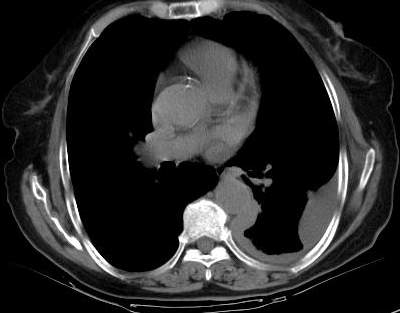

测ct值3-6hu,

既然ct值是3-6hu,还不如考虑包裹性积液。

请上传纵隔窗。目前还是支技包裹性积液(明显梭形),即使是间皮瘤并积液也少梭形的。

从图片看,包裹性积液好象更合理,梭形,ct值3-5hu(在哪看到的?);胸膜间皮瘤如此规则,不多见。

左侧背部胸膜肥厚,伴包裹性积液,不考虑间皮瘤.

同意以上各位的高见,首先考虑包裹性积液,1.胸膜间皮瘤积液量一般较大,以游离性积液更为常见,2.可以看到增厚的胸膜结节